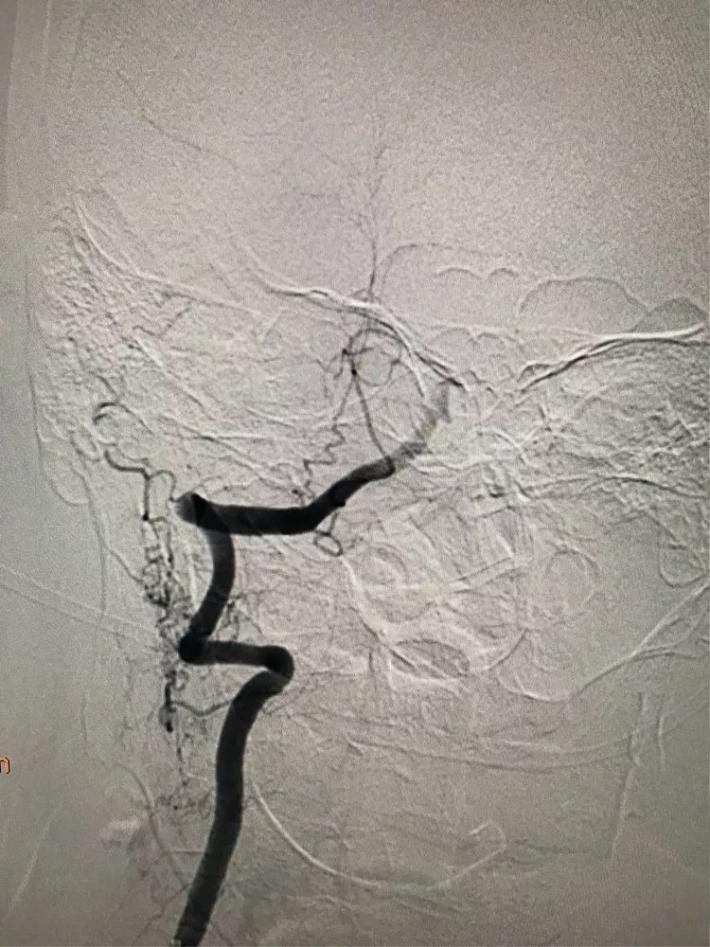

桥接动脉取栓,造影显示:基底动脉闭塞。

微导管进入基底动脉尖部,显示进入真腔。

置入支架,见基底动脉有血流。

取出支架,血管闭塞。

第二次上微导管进入真腔。

置入支架,基底动脉有血流。

取出支架,血管未开通。

第三次上微导管。

支架打开取栓。

见基底动脉血流恢复,左侧大脑后动脉血流欠佳。